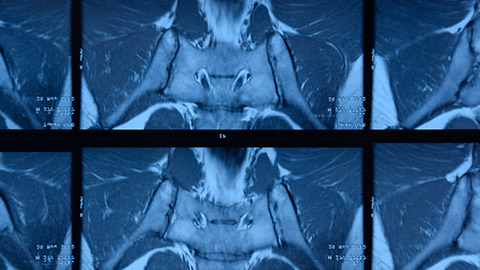

X-ray of a person with ankylosing spondylitis.

Image of Spondylitis Ankylosans

0:06:42.7 RW: There's an X-ray sign called bamboo spine that's used to describe someone who has AS, the vertebral bodies join into a single bone that looks like a fixed stalk of bamboo. I'll put a couple of Wikimedia pictures in our show notes for today to demonstrate what I mean by this. AS is a potentially dangerous disease because it can cause the spine to curve over in this really extreme flexion, it can make the ribs fused to the spine, so they don't expand and contract with breathing, that is a recipe for life-threatening pneumonia, other complications of ankylosing spondylitis range from not a big deal to really serious. Some people get irritated, itchy eyes, this is iritis during flares. Some patients get swollen hand joints and fingers, we see this with psoriatic arthritis too, and some patients, especially women have painful inflamed peripheral joints like shoulders and hips, and we heard a hint of that in our client's description. Lots of people with AS also develop osteoporosis with a high risk of spinal fractures and they may also develop heart failure because of limited space in the thoracic cavity. Ankylosing spondylitis is often, but not always linked to the presence of a particular gene called HLA-B27.